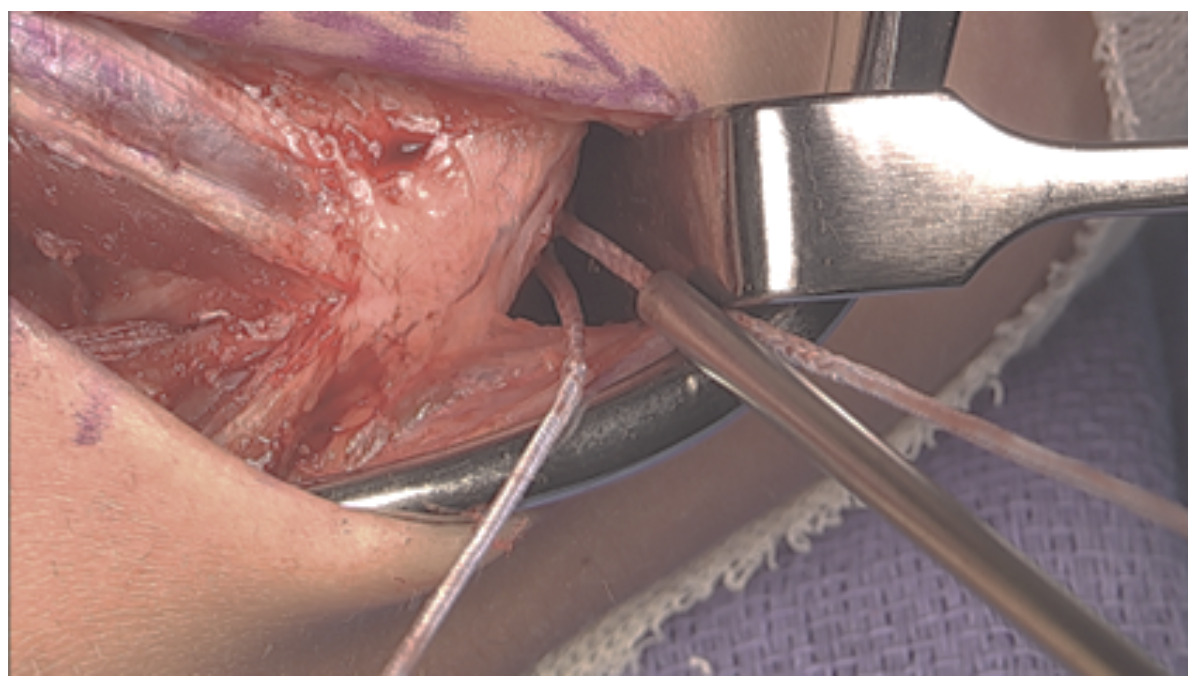

Approach

The surgical approach is made through a skin incision beginning at the upper margin of the medial epicondyle and carried distally for a typical length of 6 cm.

The superficial nerve branches are isolated and preserved.

The ulnar nerve is elevated off the proximal aspect of the medial epicondyle facilitating exposure for tunnel placement. A partial release of the medial intermuscular septum is often employed as well providing decompression of the nerve.

The posterior raphe of the flexor mass is split longitudinally along the length of the skin incision. The split utilizes the interval between the flexor digitorum superficialis (FDS) and flexor carpi ulnaris (FCU). During exposure, care is taken to preserve the anterior fascial layer of the FCU to protect both the muscle and the ulnar nerve.

After exposing the anterior bundle of the medial UCL, the ulnar nerve is internally decompressed by incising the overlying fascia of the FCU along its course down to the concavity of the proximal ulna.

Closure

The proximal tunnel lateralized typically leaves a good cuff of the native ligament to sew over the top of the brace/graft. A 2-0 vicryl suture is utilized here in a figure-of-eight fashion. A 2-0 fiber wire suture is then used more distally, bringing together the arms of the tendon graft, native ligament, and internal brace.

The wound is copiously irrigated. The posterior raphe is closed with a running 2-0 vicryl suture.